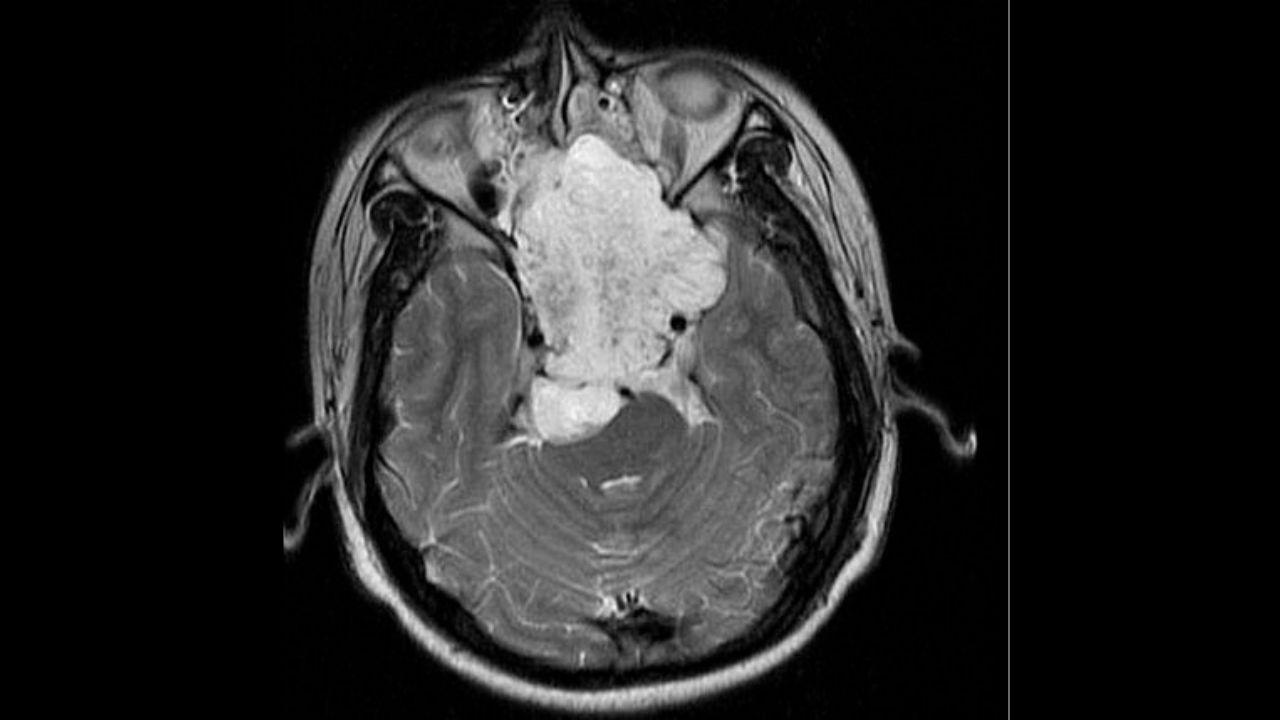

پزشک برای کمک به تشخیص محل و سایز تومور و تعیین اینکه آیا به خارج از ستون فقرات یا قاعده جمجمه گسترش یافته است یا خیر؛ نیاز به مشاهده تصاویر ام آر آی یا سی تی اسکن دارد.